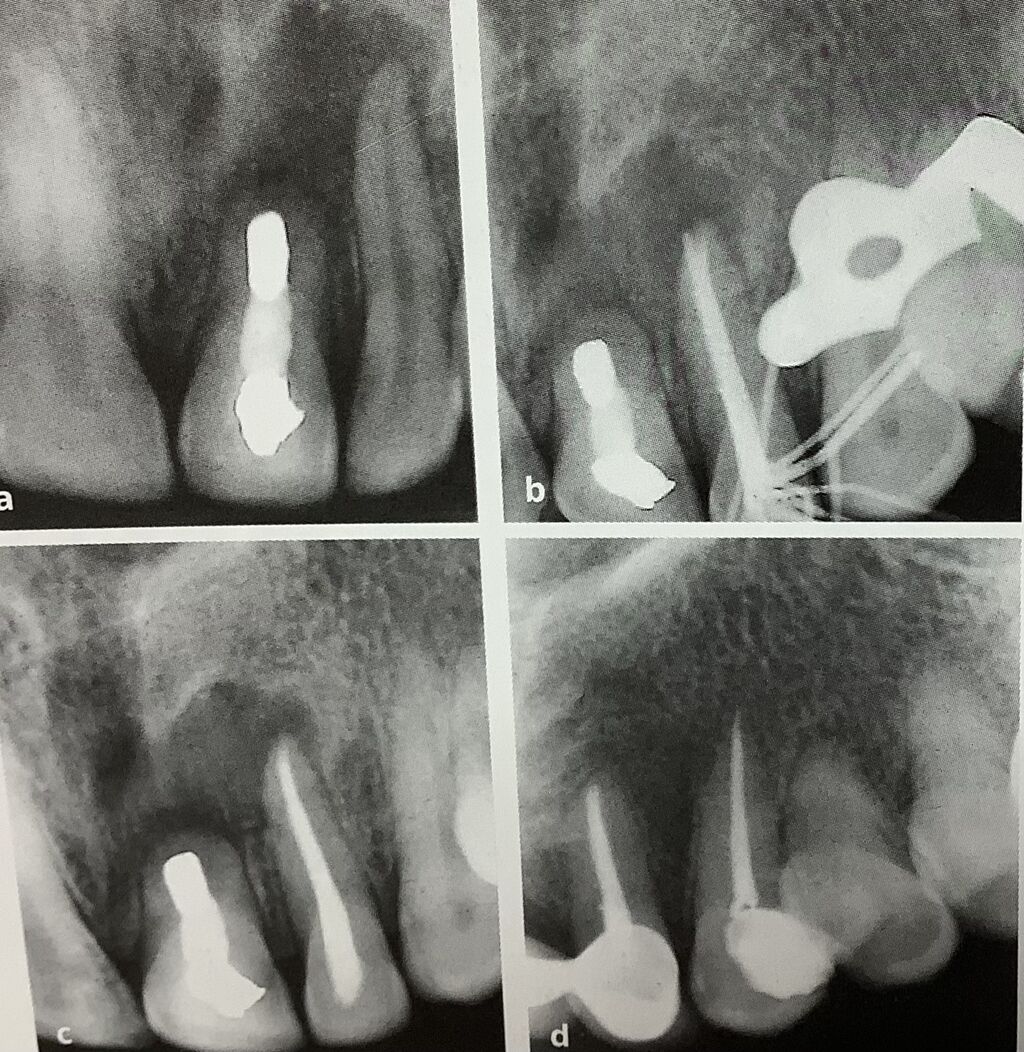

端っこに写ってる右上の2番、側切歯、

押すたり、たたくと痛い。

根っこの先の真っ白く見えてるのは、折れてる器具ですね。

真ん中のレントゲンで、この器具を取らずに、脇道が作れて尖端までキレイに出来たそうです。

で、右が治療後で、取れなくても痛みが消えれば良いので。